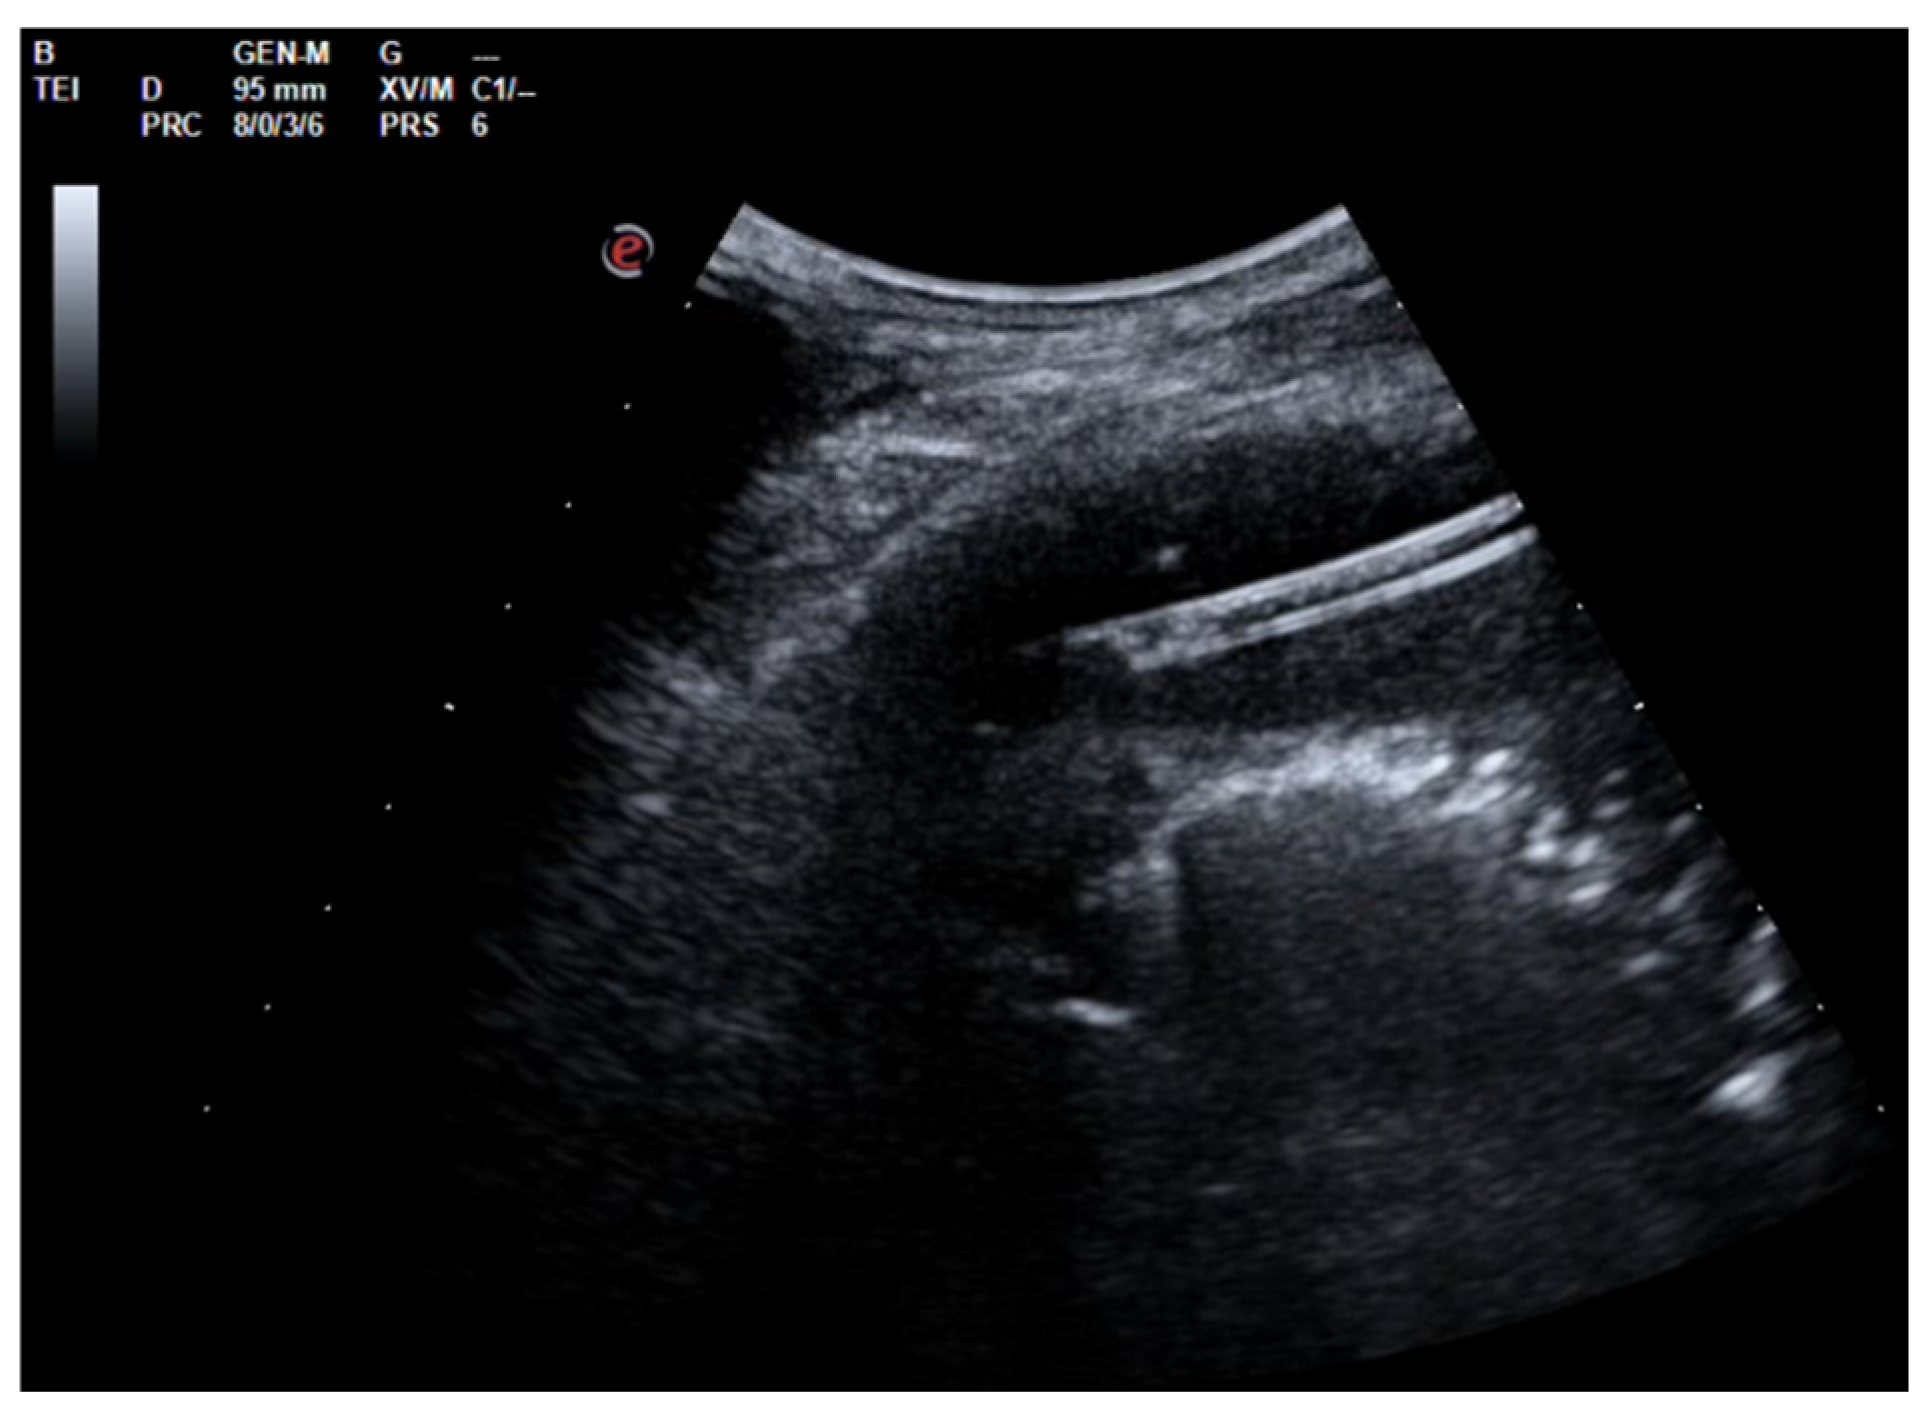

A 64-year-old Caucasian woman with iatrogenic hypothyroidism was admitted to the Respiratory Unit for worsening dyspnea, a fever, right chest pain, and coughing. The patient complained of having had a fever and dry cough for 1 week, treated with clarithromycin without improvement. Her pre-admission chest CT showed a large right PEff with lung atelectasis (Figure 8).

A chest US showed multiloculated PEff with septations of different thicknesses (Figure 9). A 12 Fr chest tube was placed, and 1000 mL of turbid fluid were drained. Samples were collected for microbiological and physicochemical analysis. Irrigation of the pleural cavity with 200,000 IU of urokinase in 50 mL of saline solution was performed under US guidance (Video 1). This was followed by the closure of the chest drain for 3 h, and then it was reopened. Further irrigation with 100,000 IU was performed 24 h later. Empiric antibiotic therapy with 500 mg azithromycin (q24h) for 6 days and 4.5 g piperacillin/tazobactam (q8h) for 2 weeks was administered. A chemical analysis of the pleural fluid revealed exudate. The microbiological study was negative.

Figure 8. Large right pleural effusion on chest CT scan.

Figure 9. Chest ultrasound at admission showing multiloculated pleural effusion.